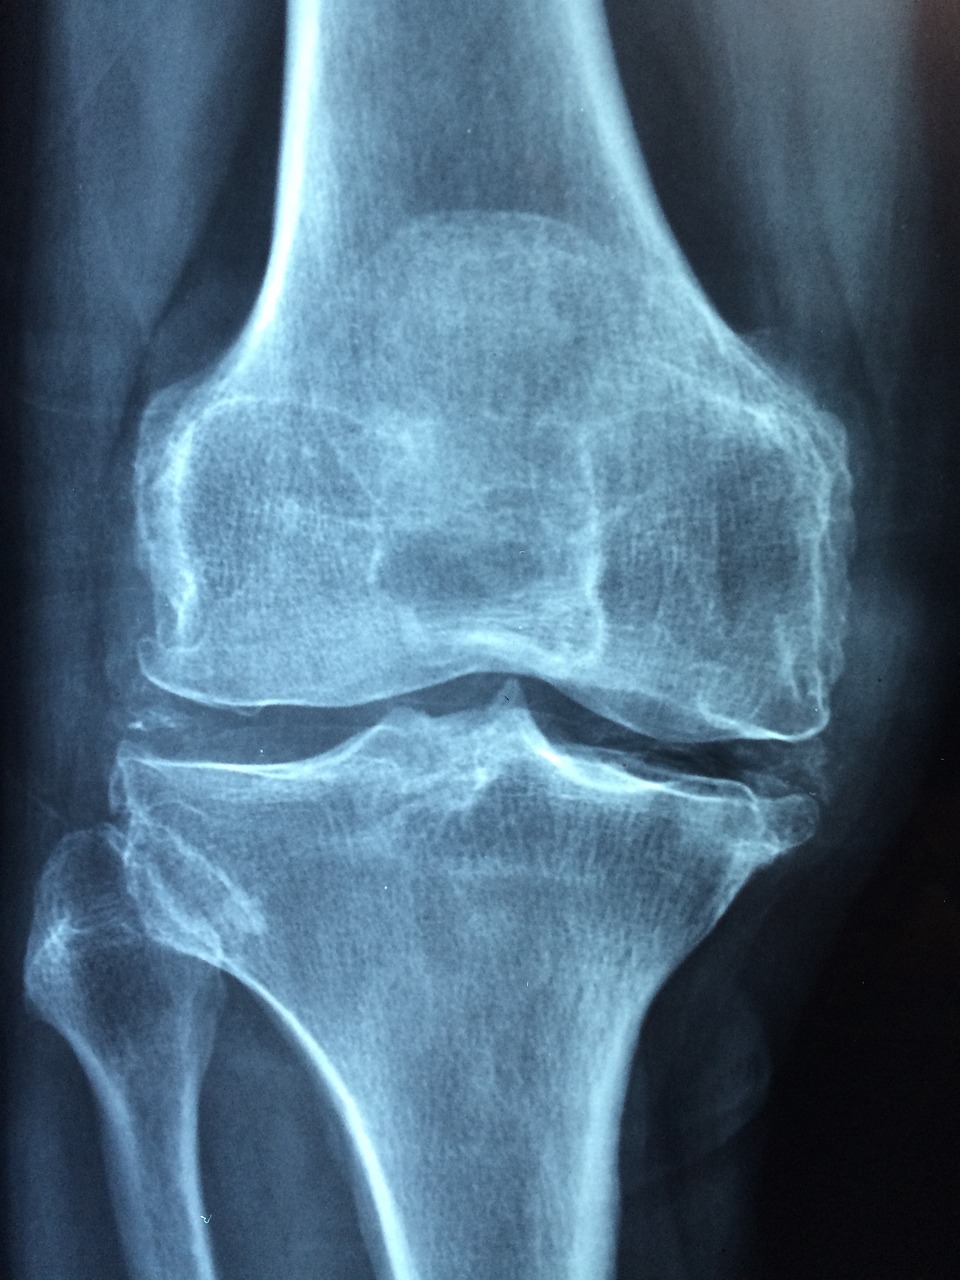

일상생활에서 불편함을 주는 류마티스 관절염은 관절과 관절 주위 조직에 만성 염증이 생기는 질환입니다. 초기에는 손가락 마디나 발가락 등 작은 관절에서부터 통증이 시작되지만 점차 팔꿈치, 어깨, 무릎관절 등 큰 관절에서도 통증이 발생하게 됩니다. 또한 아침에 일어났을 때 관절이 뻣뻣해지는 조조강직 증상이 1시간 이상 지속되는 경우도 많습니다. 이러한 증세들이 6주 이상 지속된다면 류마티스 관절염을 의심해볼 수 있습니다.

- 1. 관절 통증: 주로 손가락, 발가락, 무릎, 손목 등의 작은 관절에서 시작되며, 이후에 다른 관절로 확산될 수 있습니다. 통증은 휴식을 취하거나 움직임이 없을 때 더욱 심해질 수 있습니다.

- 4. 수술: 심한 경우, 손상된 관절을 수술로 치료하거나 교체할 수 있습니다.